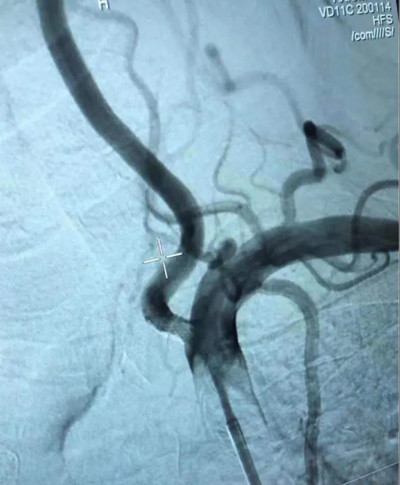

术后:左侧椎动脉血管形态基本恢复生理状态

造影结果显示患者存在后循环缺血,罪魁祸首就是椎基底动脉狭窄,雪上加霜的是患者右侧椎动脉PICA远未见显影,只有左侧椎动脉供应基底动脉血运。颅内外动脉狭窄为缺血性脑血管病重要因素,多由动脉粥样硬化所致,如果不能及时处理,将可能产生灾难性后果。冉茂胜主任医师、刘玉虎主治医师反复斟酌、推演,为切实保障患者生命安全,最大程度降低患者卒中风险,在充分与家属沟通后,最终拟定充分强化药物治疗后行左侧椎动脉支架植入术。经积极充分术前准备行左侧椎动脉起始部重度狭窄球囊扩张、支架植入术,手术过程顺利。